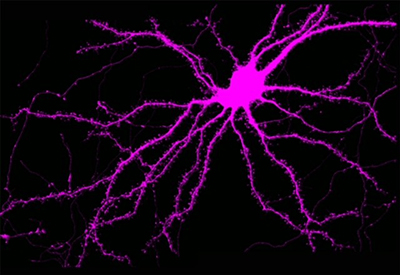

Neurons reorganize their internal structural proteins to protect themselves against acute injury. Shown here is a neuron filled with a fluorescent dye that illustrates the intricate shape that must be maintained to resist permanent loss of neuron function. Halpain Lab, UC San Diego

Neurons reorganize their internal structural proteins to protect themselves against acute injury. Shown here is a neuron filled with a fluorescent dye that illustrates the intricate shape that must be maintained to resist permanent loss of neuron function. Halpain Lab, UC San Diego